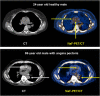

Results: They focused on coronary (n = 8), carotid (n = 7), and femoral arteries (n = 1), thoracic aorta (n = 1), and infrarenal aorta (n = 1). The remaining 15 studies examined more than one arterial segment. The literature was heterogeneous: few studies were designed to investigate atherosclerosis, 13 were retrospective, 9 applied both FDG and NaF as tracers, 24 NaF only. Subjective quality was low in one, medium in 13, and high in 19 studies. The literature indicates that NaF is a very specific tracer that mimics active arterial wall microcalcification, which is positively associated with cardiovascular risk. Arterial NaF uptake often presents before CT-calcification, tends to decrease with increasing density of CT-calcification, and appears, rather than FDG-avid foci, to progress to CT-calcification. It is mainly surface localized, increases with age with a wide scatter but without an obvious sex difference. NaF-avid microcalcification can occur in fatty streaks, but the degree of progression to CT-calcification is unknown. It remains unknown whether medical therapy influences microcalcification. The literature held no therapeutic or randomized controlled trials.

Conclusion: The literature was heterogeneous and with few clear cut messages. NaF-PET is a new approach to detect and quantify microcalcification in early-stage atherosclerosis. NaF uptake correlates with cardiovascular risk factors and appears to be a good measure of the body's atherosclerotic burden, potentially suited also for assessment of anti-atherosclerotic therapy.